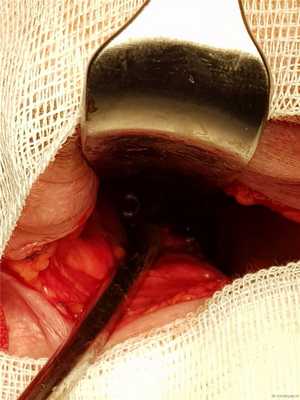

Доступ к С2 под нижней челюстью справа. Можно и слева, но правше и сподручнее справа.

Вид операционной раны с головками винтов.